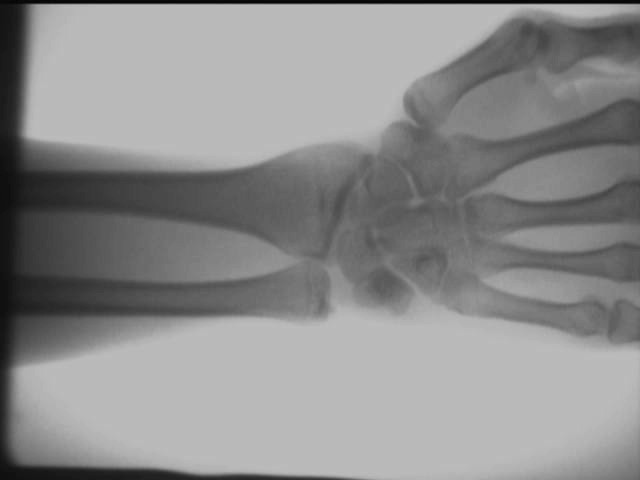

نمودار اثر آزمایش در محل آشکارساز اشعه ایکس ارتوپدی

افکت پرسپکتیو کف دست